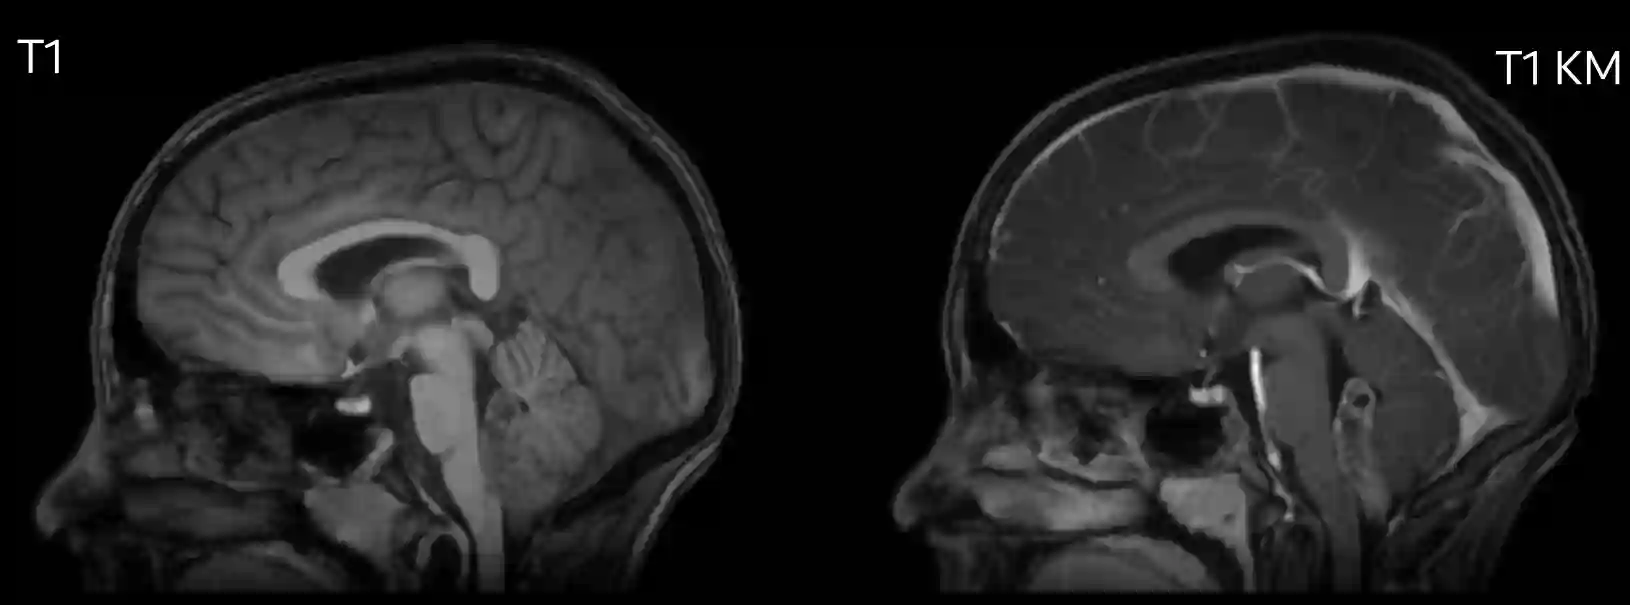

Zwei Drittel der Ependymome treten infratentoriell im 4. Ventrikel auf, das übrige Drittel liegt supratentoriell und zumeist in der periventrikulären weißen Substanz. Im Gegensatz zu einem Medulloblastom, welches häufig vom Dach des 4. Ventrikels ausgeht, breitet sich ein Ependymom oft vom Boden des 4. Ventrikels aus.

Bildgebend unterscheiden sich Ependymome von Medulloblastomen vor allem durch die häufige Kalzifikation, welche bei Medulloblastomen nur in weniger als 10 % der Fälle vorkommt[^2]. Ebenso zeigen sich Ependymome häufig inhomogen in der T1 Sequenz und die exophytische Komponente zeigen sich bei Ependymomen oft hyperintenser in der T2 Sequenz[^2]. Ependymome können in der MRT Bildgebung eine Diffusionsrestriktion aufweisen, was jedoch bei Ependymomen deutlich seltener als bei Medulloblastomen vorkommt[^4].